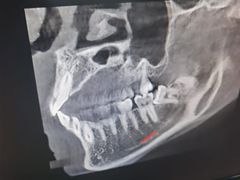

• 牙博士口腔品牌连锁(杨浦店)

• -牙博士口腔品牌连锁(杨浦店)

昊月当空 | 23-04-13

wjh_716 | 23-04-12